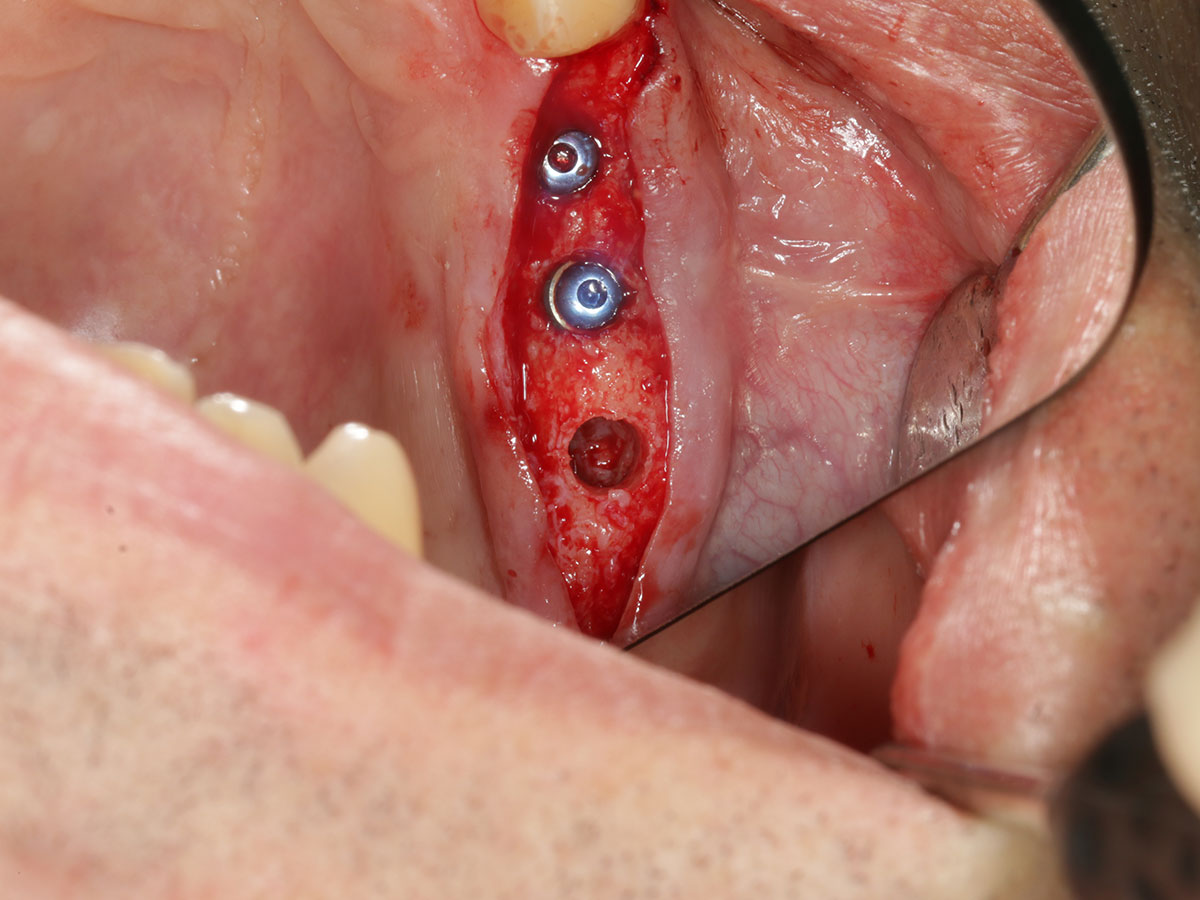

· Von der digitalen Planung zur chirurgischen Umsetzung

· Herstellung und Anwendung von Bohrschablonen

· Statische Navigation: Schritt-für-Schritt-Workflow und klinische Tipps